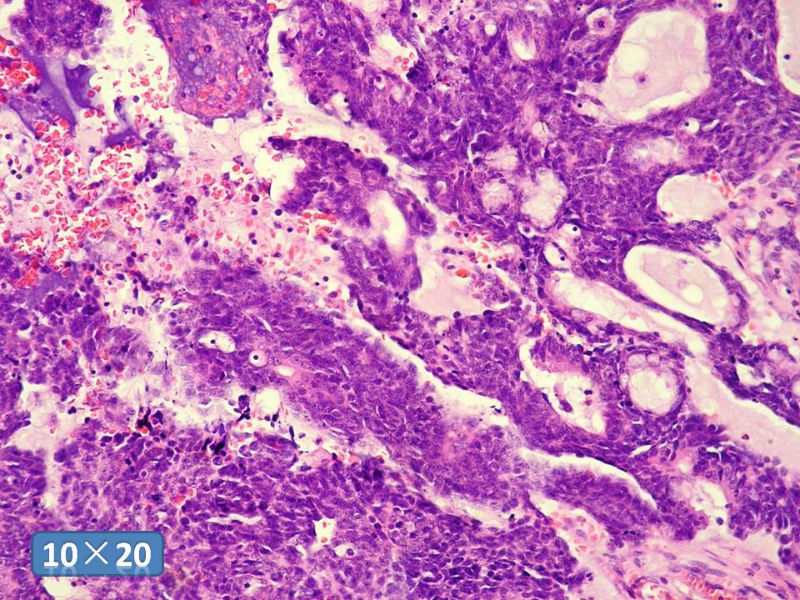

男性,49岁,间断左鼻腔出血3个月。

标签:是嗅母么?

1)嗅神经母细胞瘤?

2)腺肌上皮癌?

3)肌上皮癌?

4)神经内分泌癌?

5)腺样囊性癌?

6)其他?

腺肌上皮癌

感觉要排除畸胎癌肉瘤。

间质为恶性梭形细胞成分,其间感觉是腺体,两种成分密切相关....

免疫组化S-100的阳性区域方式...嗅母可能性大。

支持嗅神经母细胞瘤(伴有腺体分化)

嗅神经母细胞瘤

有上皮和间叶2种结构,畸胎性癌肉瘤是要考虑一下的吧!